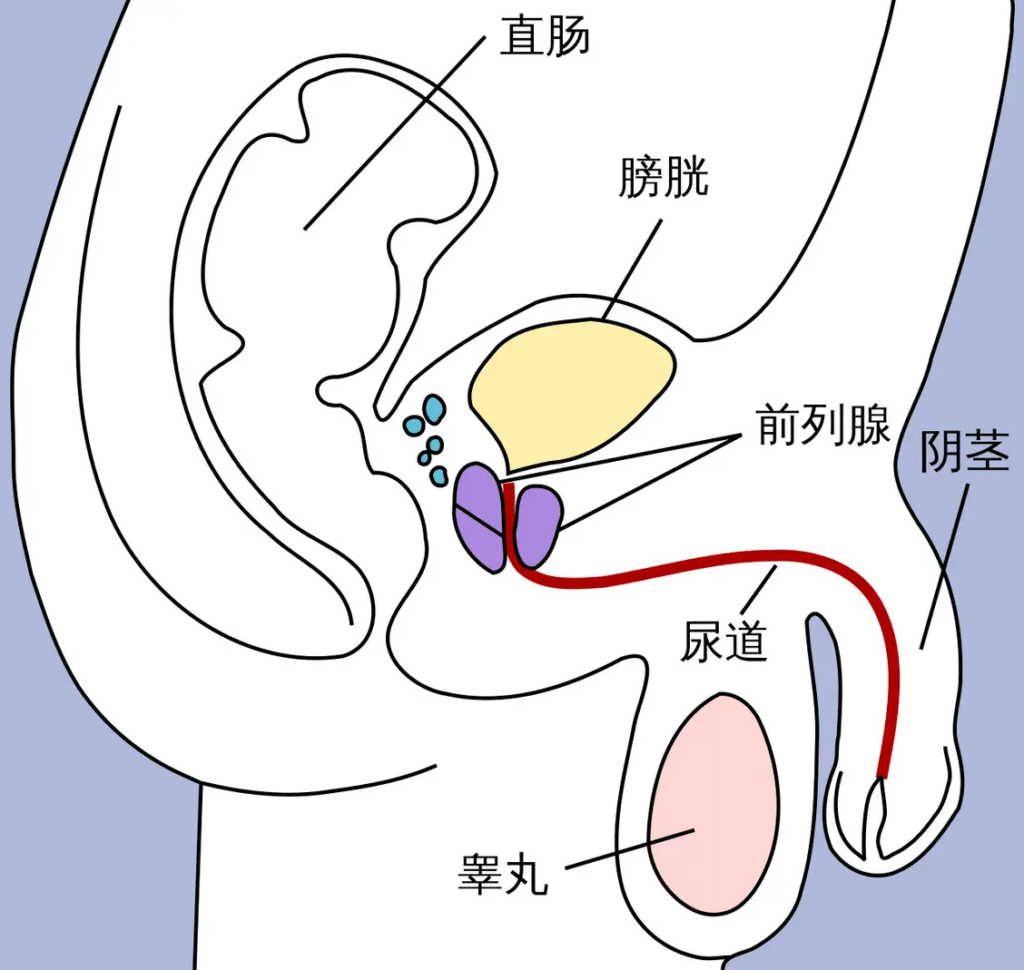

泌尿系統的解剖學差異

男生與女生的泌尿系統在結構上存在顯著差異,這直接影響排尿控制的能力。

男生尿道長約15-20厘米,從膀胱頸部延伸,經過前列腺、盆底肌群,最終至陰莖末端。尿道分為三段:前列腺尿道、海綿體尿道與膜尿道。其中,前列腺周圍有內括約肌(內尿道括約肌,為平滑肌,受自主神經控制)和外括約肌(外尿道括約肌,為骨骼肌,可任意控制)。這些括約肌確保尿液在適當時機排出。女生尿道則較短,僅約3-5厘米,從膀胱頸部直接延伸至陰道前壁開口。女生同樣擁有內外括約肌,但由於尿道短且靠近陰道與直腸,外部壓力(如懷孕或分娩)更容易影響控制。

根據解剖學描述,男生尿道較長確實提供額外阻力,但這並非「說停就停」的首要原因。關鍵在於外括約肌的強度與盆底肌群的協調。研究顯示,兩性皆可透過收縮盆底肌(Kegel運動)中斷尿流,但女生因解剖位置,較易受激素變化影響而導致肌力減弱。

女性的尿道開口在陰唇內,並非像男性一樣離身體有一段距離,而且尿道的方向向下。

尿道長度與壓力傳導

男性尿道長,尿液在排出過程中需經過較長的通道,這為外括約肌提供了更多的控制點。女性尿道短,尿液一旦進入尿道,較難被「拉回」。